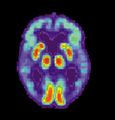

مسح PET لمخ مصاب بمرض ألزايمر - الصورة مقدمة من مركز الإحالة والتوعية بمرض ألزايمر التابع للمعهد الوطني للشيخوخة بالولايات المتحدة.

مرض ألزايمر هو مرض تنكسي وقاتل يصيب المخ، حيث تُفقد الاتصالات الخلوية بخلايا المخ. يعتبر مرض ألزايمر من أكثر أنواع الخرف شيوعاً.[2] عالمياً، يصاب بمرض ألزايمر حوالي 1-5% من السكان.[3] تقع النساء بشكل غير متناسب ضحايا لمرض ألزايمر، مع وجود أدلة تشير إلى أن النساء المصابات بمرض ألزايمر يظهرن ضعفاً إدراكياً أكثر حدة مقارنة بالذكور المصابين بالمرض، بالإضافة إلى معدل أسرع من التدهور السلوكي.[4]